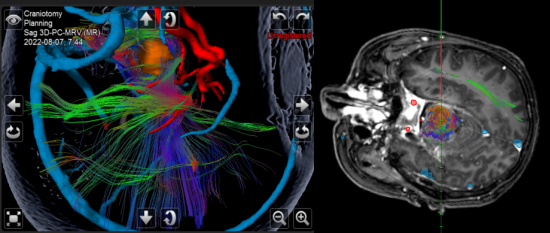

图2多模态融合技术显示手术入路及肿瘤与周围血管神经的关系,为安全切除肿瘤提供引导

高成教授团队制定了详细的手术方案,并利用最先进的神经导航设备对病变进行了定位,同时对周边控制运动和感觉的神经纤维束、核团进行了细致评估。考虑到病变位置深在,显微镜有视野盲区,内镜可以弥补其不足,高成教授团队决定采取双镜联合技术。